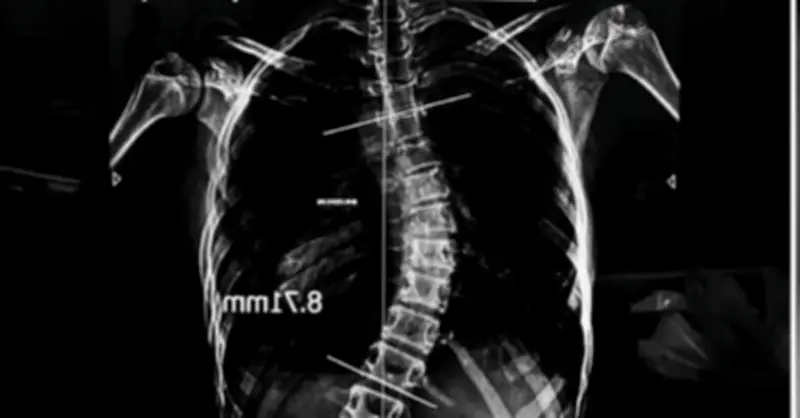

Cong vẹo cột sống là một bệnh lý phổ biến, đặc biệt ở lứa tuổi đang phát triển. Các chuyên gia y tế cho biết, bệnh có thể gây ra nhiều biến chứng nghiêm trọng như đau lưng, khó thở, và ảnh hưởng đến thẩm mỹ. Việc điều trị thường kéo dài và tốn kém, bao gồm các phương pháp như vật lý trị liệu, đeo đai chỉnh hình, hoặc phẫu thuật trong trường hợp nặng.

Chi phí cho một ca phẫu thuật chỉnh hình cột sống có thể lên đến hàng tỷ đồng, tùy thuộc vào mức độ phức tạp và cơ sở y tế. Nhiều gia đình phải vay mượn, tích góp nhiều năm để trang trải, trong khi một số khác tìm kiếm sự hỗ trợ từ các chương trình bảo hiểm hoặc từ thiện.

Với sự phát triển của y học hiện đại, nhiều phương pháp điều trị ít xâm lấn và hiệu quả hơn đang được áp dụng. Các kỹ thuật phẫu thuật bằng robot hoặc sử dụng vật liệu sinh học giúp giảm thiểu rủi ro và thời gian hồi phục. Tuy nhiên, chi phí cho những phương pháp này vẫn còn cao, đòi hỏi sự đầu tư lớn từ gia đình và xã hội.